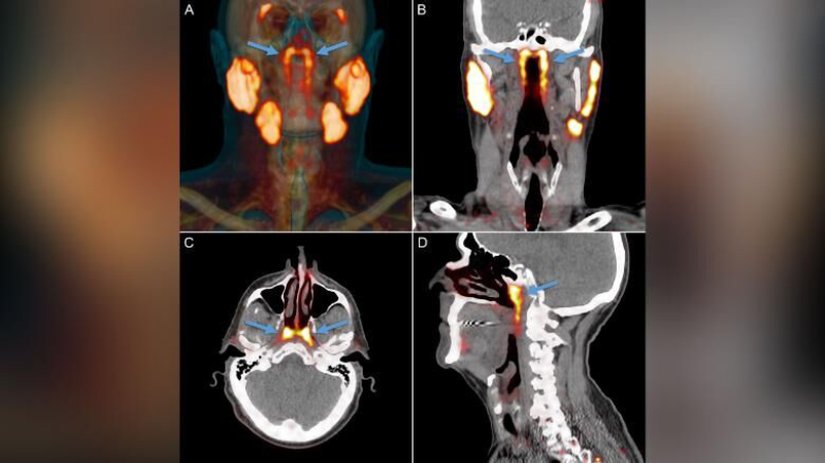

Hollanda Kanser Enstitüsü'nde prostat kanseri hastalarında yapılan çalışmada, görüntüleme yöntemleri ile daha önce tanımlanmamış bir çift tükürük bezi varlığından şüphelenildi. Prostat spesifik membran antijen ligandları (PSMA) işaretlenmiş 100 hasta, pozitron emisyon tomografisi/bilgisayarlı tomografi (PET/BT) altında görüntülendi. Ardından nazofarinks (geniz) bölgesinde daha önce bilinmeyen bilateral (çift taraflı) yeni tükürük bezleri tanımlandı.

100 hasta ve 2 kadavra incelemesinde, sınırları belirlenmiş, ortalama uzunluğu 3.9 cm olan iki taraflı PSMA-pozitif alanlar görüldü.[1]Çalışma, Radiotherapy and Oncology akademik dergisinde yayımlandı. Histolojik (doku bilimi) incelemeler ve 3D rekonstrüksiyonları PSMA eksprese eden, baskın olarak torus tubarius yakınında, çok sayıda drenaj kanallarına sahip ağırlıklı olarak müköz bezlerinin varlığını doğruladı. Bu bölgeye alınan yüksek doz radyoterapi sonrası hastalarda kserostomi (ağız kuruluğu) ve disfaji (yutma güçlüğü) görülmesi, daha önce bilinmeyen bu bezlerin zedelenmesine bağlı olarak açıklanabilir.